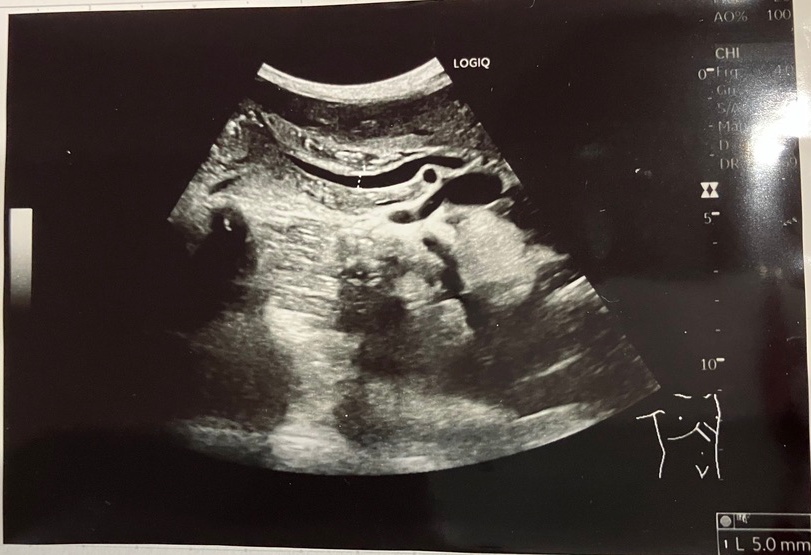

で、今回の症例のエコー像はというと…

総胆管は最大8mmほどで、その抹消側は緩やかに細くなっていきます。

CBDをファーター乳頭近くまで観察しましたが明らかな閉塞起点は分からず…、

また主膵管(PD)との合流部もエコー上、はっきりと描出できませんでした。どう頑張っても、CBDも主膵管(PD)も十二指腸開口部付近までそれぞれ単独で追えてしまう。

膵・胆管合流異常は、CBDとPDが合流してファーター乳頭に開口するまでの管(共通管)があるはずなのだけれど、どう頑張ってみても、共通管は見つからなかった…泣

膵管(PD)もいつものエコー時よりもはっきりと描出されるので、膵管軽度拡張(+)にしたいところですが、膵体部でのMPD径は2.7mm程なので、基準範囲内ではある…。

膵管の走行はスムーズです。

副膵管も、普段は見えないものが見えている時点で、軽度拡張(+)にしたいところですが、計測すると1.7mmくらいなので、拡張とは取れませんよね…?